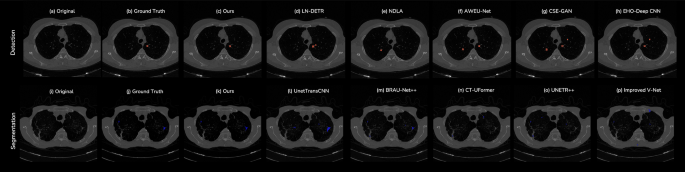

To establish the performance of GLANCE relative to the current state-of-the-art, we conducted an extensive comparative analysis against a wide range of recently published models on four standard public benchmarks. The evaluation was performed separately for segmentation (on LIDC-IDRI and LNDb) and detection (on LUNA16 and Tianchi), with the comprehensive results presented in Table 2 and Table 3. Fig. 1 displays our model along with visual segmentation and detection results from recent SOTA models. The findings from this benchmarking exercise consistently position GLANCE as a new leading method in both domains.

For each case, we show the original image, ground truth, ours, and a series of baselines arranged left-to-right in progressively worse visual quality relative to (c)(k)ours. Detection baselines: (d)LN-DETR, (e)NDLA, (f)AWEU-Net, (g)CSE-GAN, (h)EHO-Deep CNN, segmentation baselines: (l)UnetTransCNN, (m)BRAU-Net++, (n)CT-UFormer, (o)UNETR++, (p)Improved V-Net; Our method yields sharper boundaries and fewer false positives/negatives, with competing methods exhibiting increasing boundary erosion, missed lesions, and spurious responses to the right.